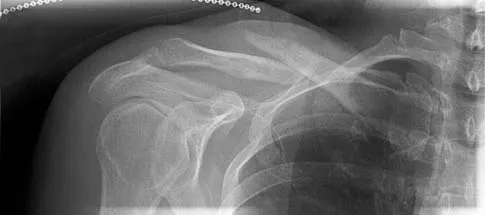

A 53-year-old patient is seen in the emergency department after sustaining a fall onto her left hip. A current radiograph is shown in Figure 40. What is the best treatment option?

The patient has sustained a Vancouver B2 periprosthetic femoral fracture (a femoral fracture that occurs around or just distal to a loose stem, with adequate proximal bone stock). The stem is no longer fixed to proximal bone; therefore, retention of the femoral component is not recommended. Nonsurgical management is contraindicated because of the high risk of nonunion and malunion with significant component settling in the distal fragment and leg shortening. Revision femoral arthoplasty must attain distal fixation in adequate host bone, which is usually successful with a porous-coated cylindrical stem. Parvizi J, Rapuri VR, Purtill JJ, et al: Treatment protocol for proximal femoral periprosthetic fractures. J Bone Joint Surg Am 2004;86:8-16.